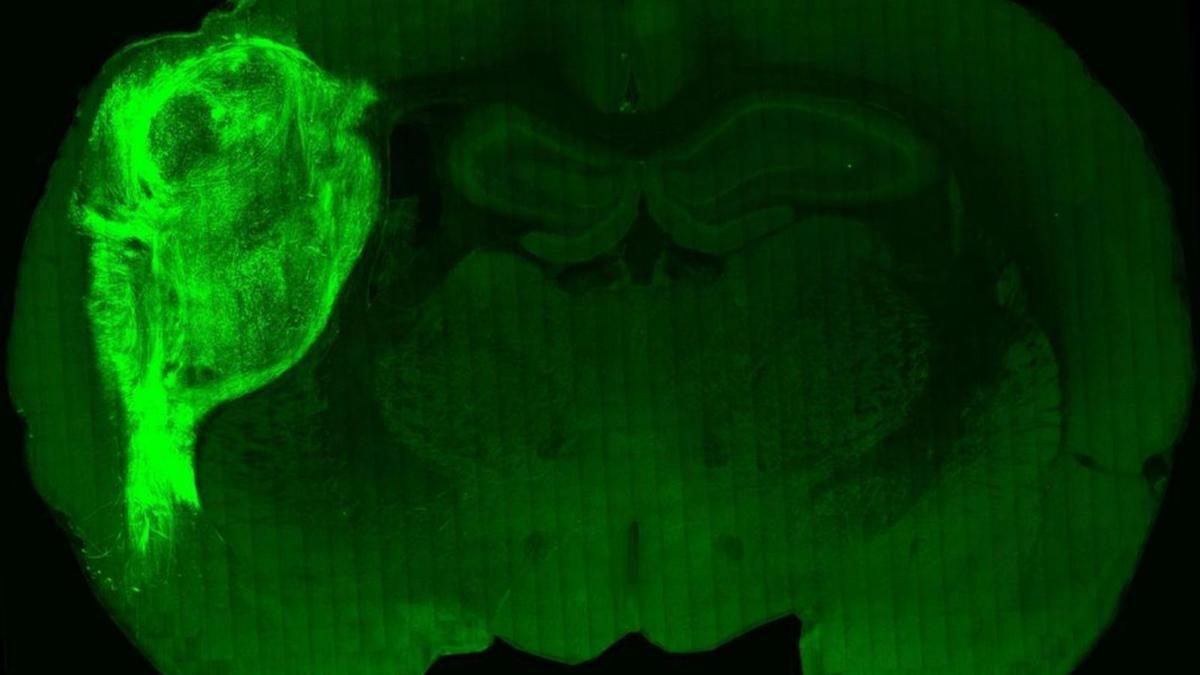

No és la primera vegada que s’aconsegueix crear un minicervell en un laboratori. Ja hi ha grups de recerca que ho han aconseguit. Però, a diferència d’estudis anteriors, aquesta és la primera vegada que s’aconsegueix crear un òrgan in vitro, trasplantar-lo a un rosegador, observar com els teixits humans s’integren amb els de l’animal, s’estableixen connexions neuronals noves i es desenvolupen cèl·lules típicament humanes en el cervell d’una rata. Mai abans una recerca havia aconseguit una successió d’èxits així.

En primer lloc, els científics van collir un minicervell a partir de cèl·lules mare humanes. Una vegada creat aquest òrgan el van trasplantar a una rata d’entre 3 i 7 dies. Els teixits humans es van inserir just en un moment en què el cervell de l’animal estava en període de desenvolupament. D’aquí ve que, segons apunten els autors d’aquesta recerca, s’aconseguís connectar les cèl·lules humanes amb les del rosegador. El procés s’ha fet amb cèl·lules de pacients amb la síndrome de Timothy: una malaltia congènita que afecta el neurodesenvolupament. El trasplantament d’aquestes cèl·lules en animals nounats ha permès estudiar les primeres etapes de desenvolupament de les cèl·lules, el comportament i l’impacte sobre l’activitat neuronal. «L’estudi va mostrar que les neurones dels organoides tenien morfologies menys elaborades, així com diferents connexions sinápticas i una activitat elèctrica modificada», diuen els experts en bioenginyeria J. Gray Camp i Barbara Treutlein a la revista ‘News & views’.